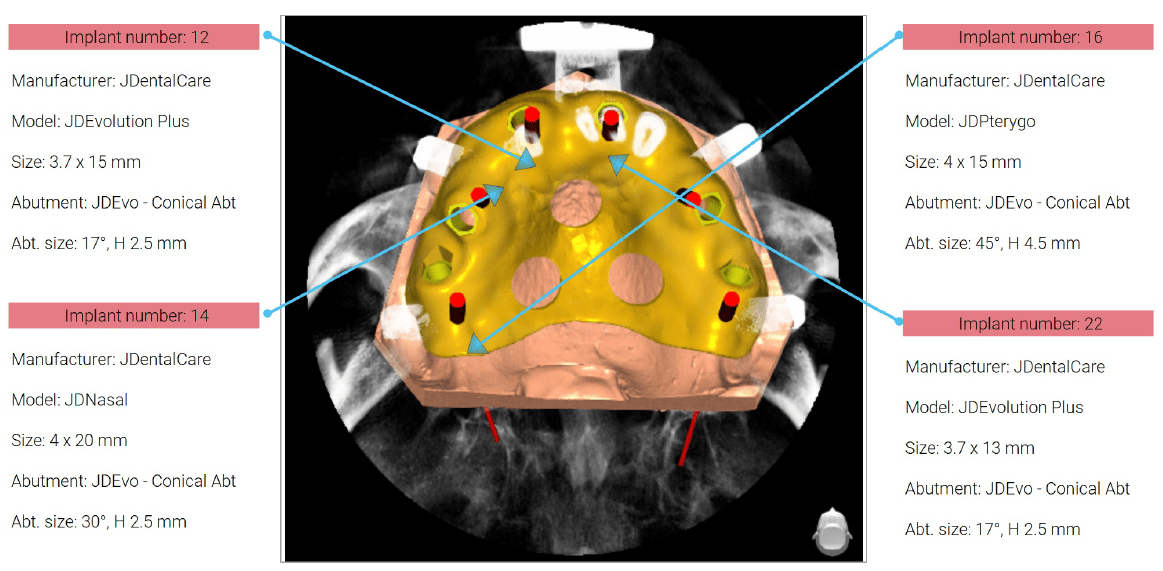

Η θεραπεία με πτερυγοειδη εμφυτεύματα είναι μια πρωτοποριακή διαδικασία που περιλαμβάνει την τοποθέτηση οδοντικών εμφυτευμάτων στο πτερυγοειδές οστό, το οποίο βρίσκεται πίσω από την άνω γνάθο, παρέχοντας μια βιώσιμη λύση για ασθενείς με σοβαρή οστική απώλεια στην άνω γνάθο, οι οποίοι διαφορετικά δεν θα ήταν κατάλληλοι για θεραπεία με οδοντικά εμφυτεύματα. Επιλέξαμε τα εμφυτεύματα JDPterygo από την JDentalcare, Ιταλία.

Εκτός αυτού, χρησιμοποιήσαμε εμφυτεύματα JDnasal στη ρινική περιοχή: